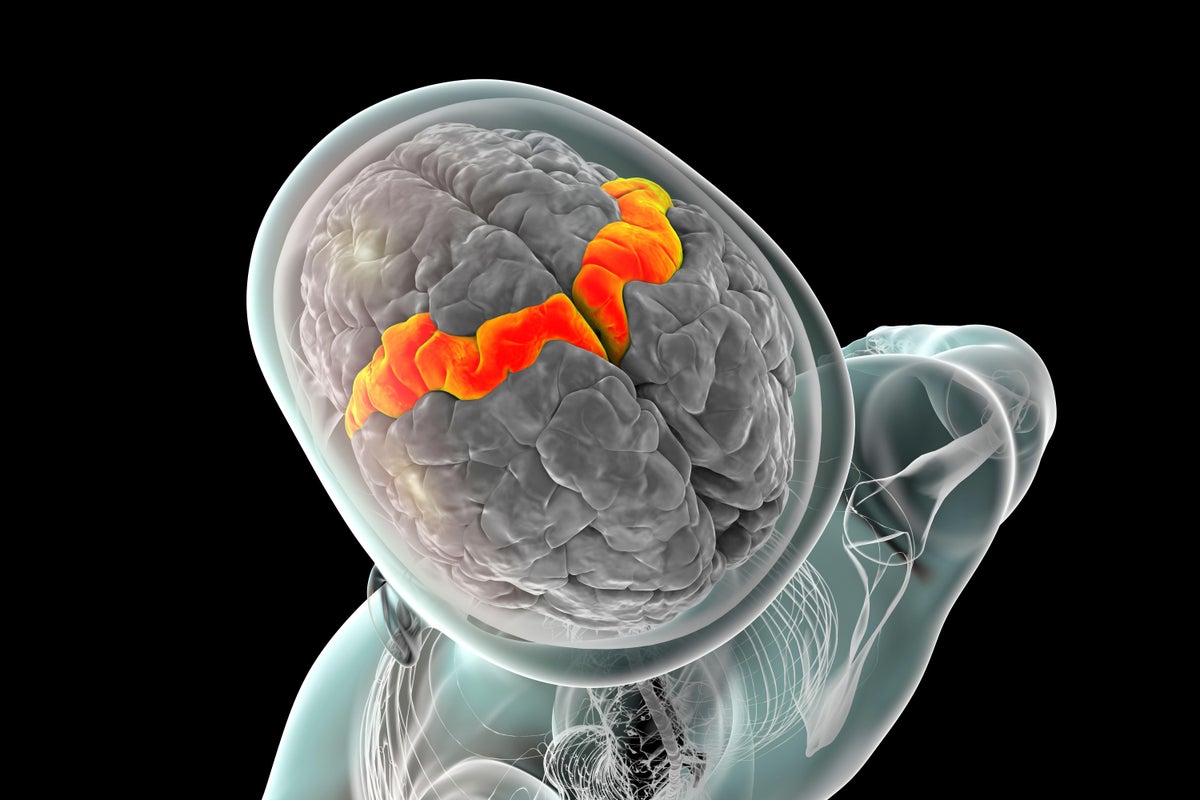

La corteza del motor (naranja, ilustración). Los electrodos implantados en esta región ayudaron a registrar la actividad cerebral relacionada con el habla de un hombre que no podía hablar de manera inteligible.

Kateryna Kon/Biblioteca de fotos de ciencias/Alamy Stock Photo